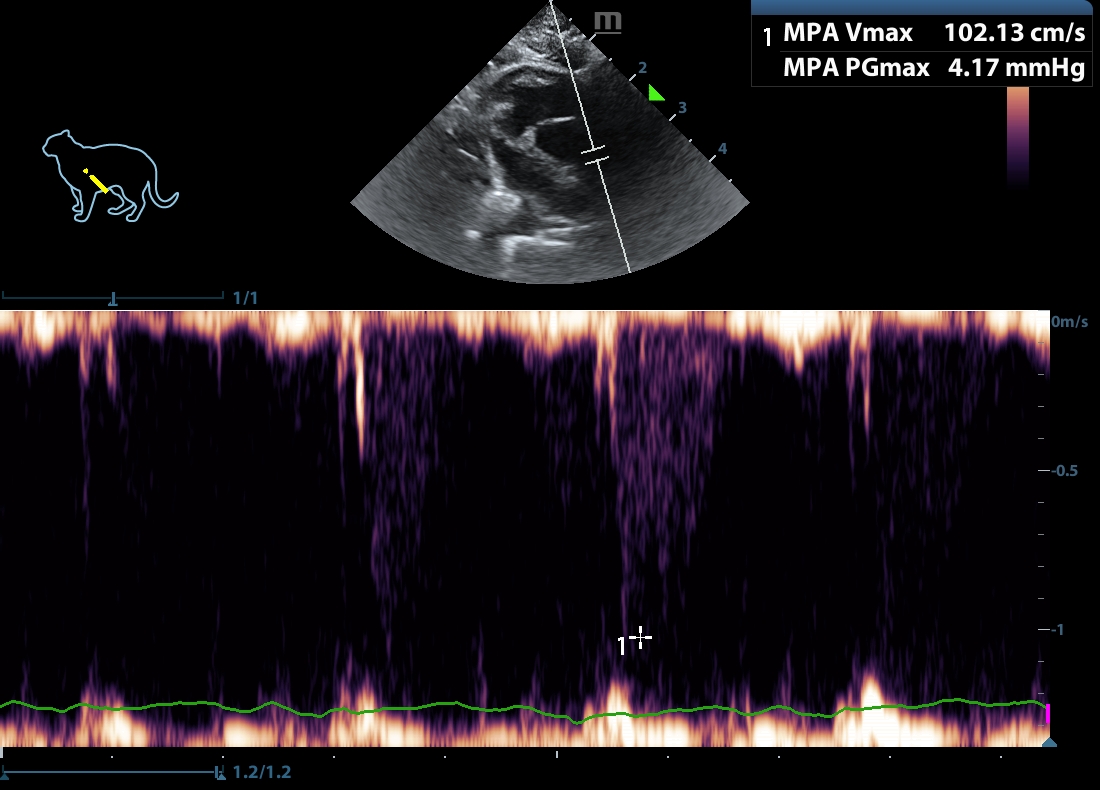

202505231604490135CARD.JPG